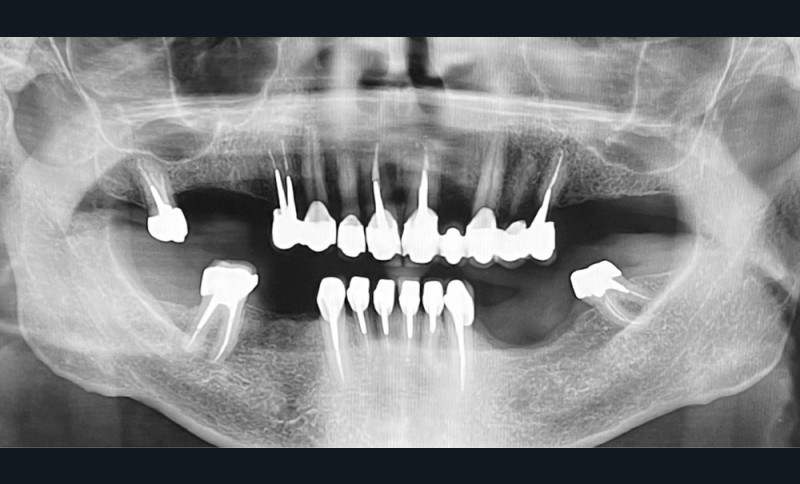

à l’examen endo-buccal, le patient présente un édentement de classe II de Kennedy modification 1, compensé par une prothèse amovible partielle composite en cobalt-chrome (fig. 1a et 1b). On note la présence de glissières de semi-précision parallèles PDC II (Afinor) entre 14-15 et entre 23-24, apportant guidage, stabilisation, sustentation et rétention par effet de coin. Au niveau mandibulaire, le patient présente un édentement de classe III modification 2 avec des crêtes de classe 3 selon la classification de Cawood et Howell, associées à une muqueuse ferme et adhérente (fig. 1c). L’insertion du frein lingual et labial, ainsi que des brides musculaires sont à distance. On note la présence de couronnes fraisées en 38 et en 46, l’absence de lésions apicales actives à l’examen radiographique (fig. 2), et une mésioversion de la 38 prenant la place de la 37.